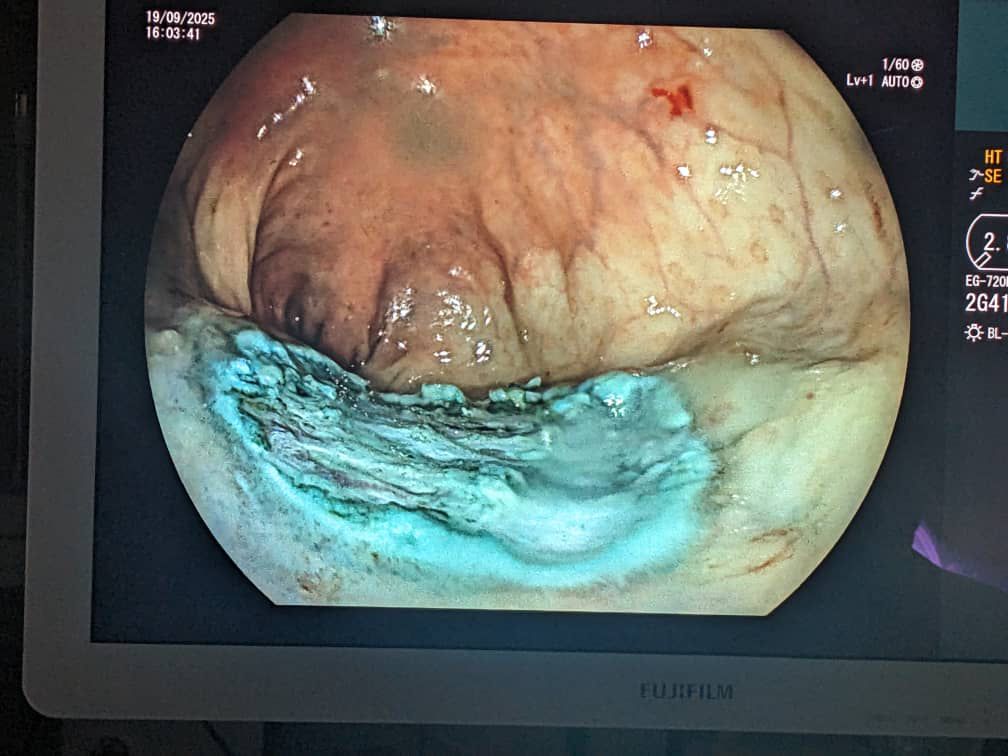

Ubu buryo kandi uretse kuba busimbura kubagwa, bunasimbura ibindi bisanzwe bikorerwa abafite iyi kanseri nko gushiririza agace iyo kanseri yafashe.

Gusa nanone ubu buvuzi bushoboka mu gihe ufite kanseri ikiri ntoya itarakwirakwira mu bice byose.

Ubu buryo bw’ubuvuzi bwatangiriye mu Buyapani mu myaka irenga 20 ishize, aho bwakomeje gutezwa imbere no kwemezwa nk’uburyo bunoze mu kuvura kanseri z’imbere mu mubiri zigaragaye hakiri kare.

Nyuma bwaje gukomeza gukoreshwa mu bindi bihugu nka Koreya y’Epfo, u Bushinwa, ndetse no mu bihugu by’u Burayi n’Amerika.

Mu bushakashatsi buheruka gukorerwa mu Buyapani, byagaragaye ko abagera ku 140,000 bakorewe ubu buvuzi, 90% yabo barakize.

Gukorwa bwa mbere kwa ESD mu Rwanda ni igikorwa cyerekana ko igihugu gikomeje gutera imbere mu gukoresha ikoranabuhanga mu buvuzi no kuvura indwara zikomeye nka kanseri yagaragaye kare.